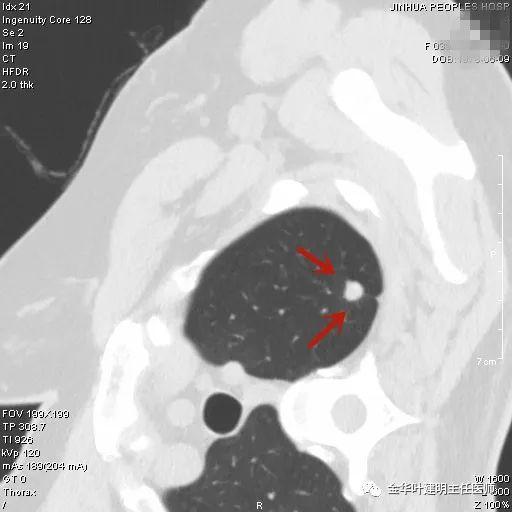

叶建明谈结节:检查发现肺实性结节怎么办?个人版实用指南

上图是纤维增生,但我们看病灶有明显的叶间胸膜牵拉,虽然力度弱,但这么小的病灶能指望它有多少力度呢?恶性还是不能除外的。